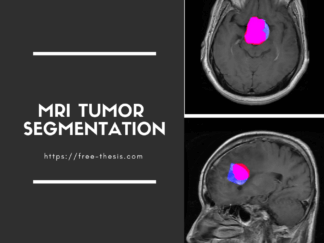

- The extracted tumor will be highlighted in red color and Blue color is the true tumor.